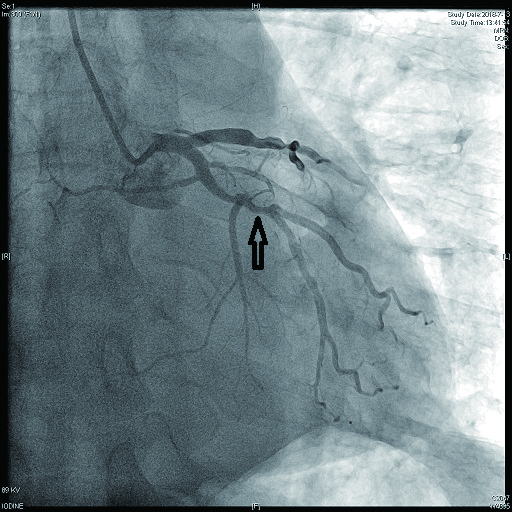

病例2 3(图 6~8 LAD近段 次全闭塞 2级 LAD近段植入支架1枚

图 6 病例2冠脉造影示LAD中段病变

图 7 病例2冠脉造影示LCX病变

图 8 病例2冠脉造影示RCA病变